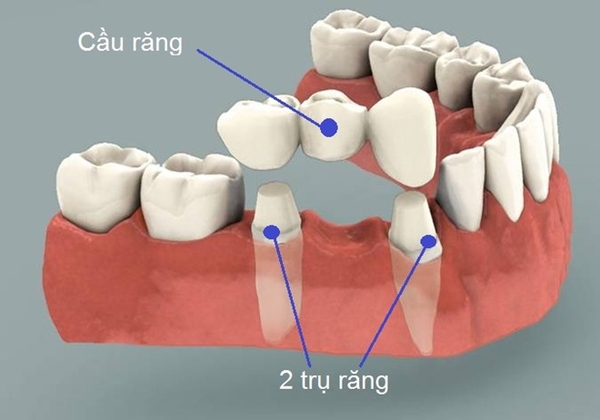

Cách làm cầu răng

Cầu răng là cách làm kinh điển, răng giả được gắn cố định vào răng thật bên cạnh...